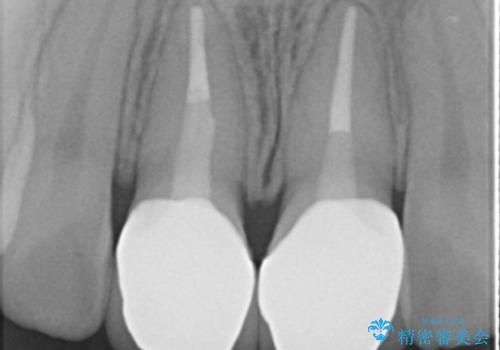

- 神経のない前歯が変色していたため、矯正治療後にセラミックで修復しました。

セラミックの前に、全体をオフィスホワイトニング(エクセレント)して周りの歯を白くして色をなじませました。

右の前歯は当院で根管治療をやり直しています。(根管治療はDr.大元が担当しました。)

- 38万円(上顎両側1:ジルコニアクラウン スタンダード 10万円x2、ファイバーコア 2万円x2、 精密根管治療(再治療)9万円x1、仮歯 1万円x2)、ホワイトニング(エクセレント)3万円費用は治療当時の料金となります